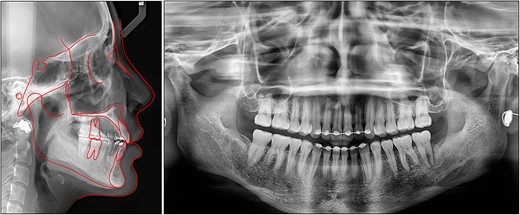

On a lateral cephalometric evaluation, the patient had a skeletal class I relationship (point A-nasion-point B angle, 4.0°) with a hyperdivergent facial pattern (Frankfort mandibular angle, 32.5°) (Table 1). The panoramic radiograph showed the presence of all teeth including the third molars (Fig. 2). The patient was diagnosed with an iatrogenic open bite and class II malocclusion on a skeletal class I relationship.

After treatment, class I canine and molar relationships were obtained on both sides with a normal overjet and positive overbite (Fig. 5). The posttreatment lateral cephalometric evaluation showed an improvement in both anteroposterior (point A-nasion-point B angle, 3.1°) and vertical dimensions (Frankfort mandibular angle, 31.0°). The posttreatment panoramic radiograph showed adequate root parallelism without any sign of root resorption (Fig. 6). The lateral cephalometric superimpositions confirmed the intrusion of the maxillary molars, the extrusions of the incisors, and the counter-clockwise autorotation of the mandible (Fig. 7).